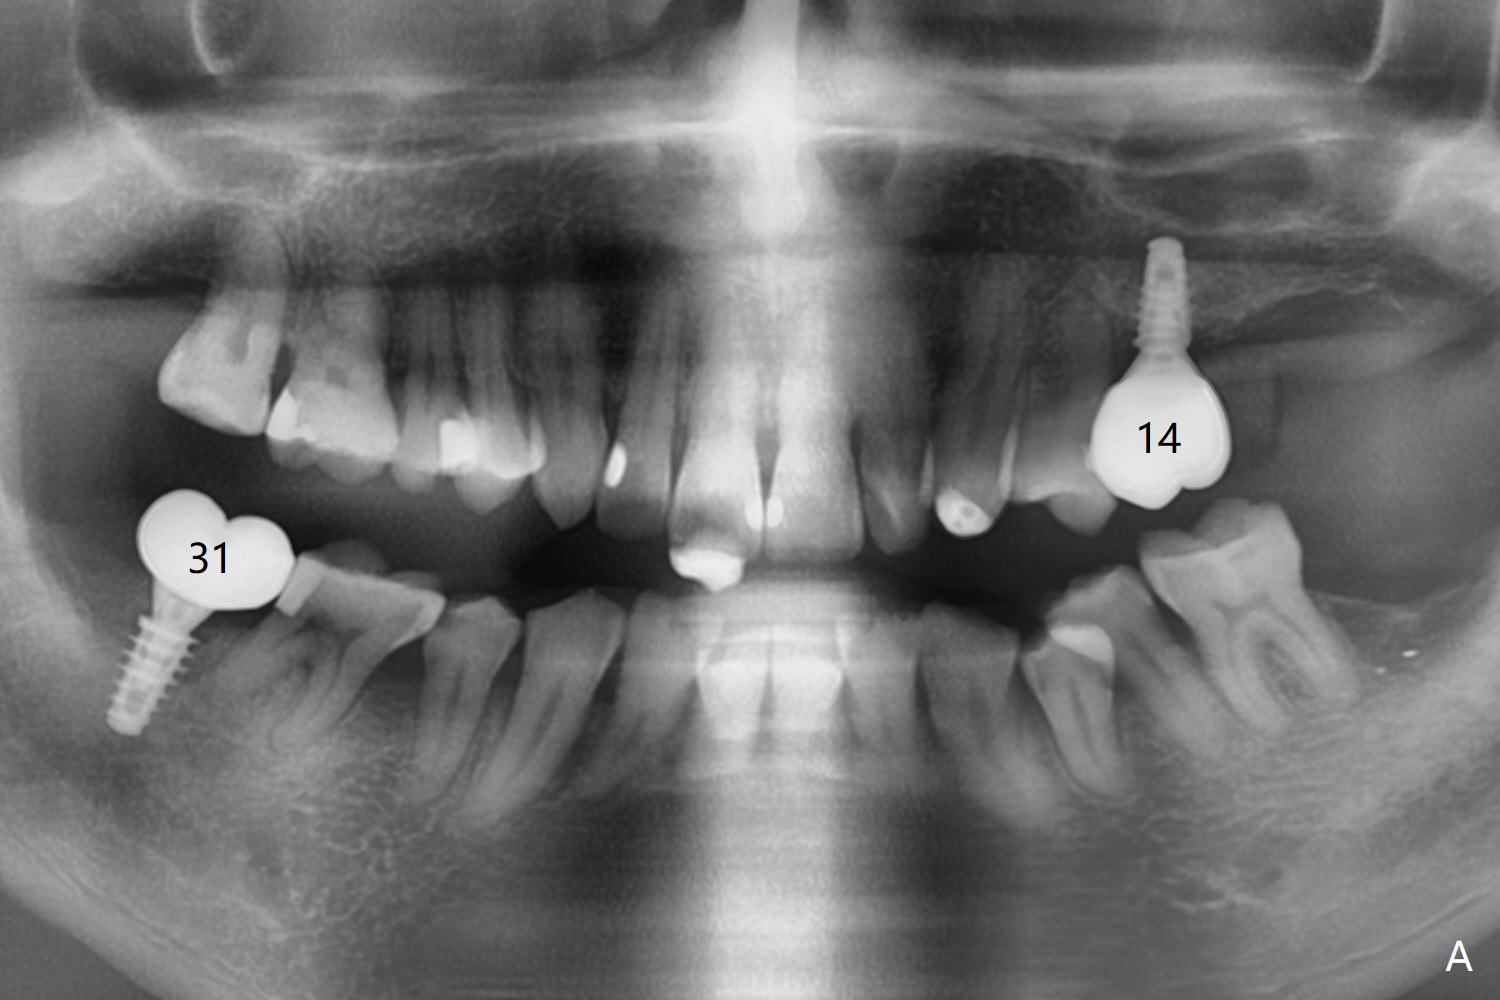

A 54-year-old man remains difficult in mastication in spite of implant placement at #14 and 31 (Fig. A, B, E, including screw loosening (poor trajectory at #14)). In addition to 2 more implants at #15 and 18 with guide, malocclusion seems to be necessary to be addressed (Fig.1-5). It appears that UR, LL4 should be extracted for orthodontic treatment (Fig.6-10). To reduce screw loosening, IS guide will be used to place IBS (5x9mm) and tissue-level (5x11mm) implants at #15 (PRF)and 18, respectively. If the one at #14 or 15 keeps loosening, splint #14 and 15 crowns. In fact the patient agrees with limited ortho (UR7 cross bite).